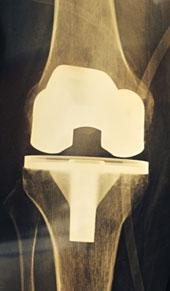

Тотальное эндопротезирование коленного сустава

Данный подход включает полную замену сустава с полным охватом всех сочленений большеберцовой и бедренной костей, а в некоторых случаях и надколенника. Этот тип операции является наиболее распространённым, поскольку при различных заболеваниях поражения чаще всего затрагивают все суставные поверхности.